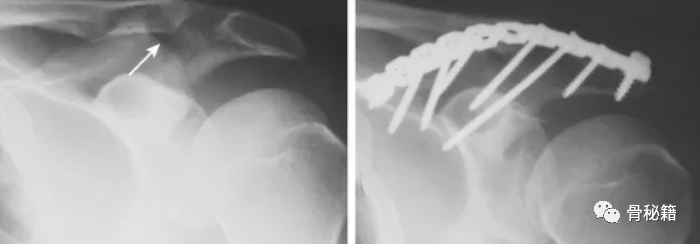

肩峰粉碎骨折,采用钢板螺钉固定,完成悬吊复合体的稳定

肩峰骨折 移位明显,采用钢板固定

也可以采用克氏针张力带技术固定

肩峰骨折是一种罕见的损伤,由于目前的文献缺乏关于手术治疗的标准化临床指南,因此治疗起来可能具有挑战性。在这种创伤性完全后肩峰骨折合并锁骨远端骨折的病例中,出现了不稳定的肩峰复合体。对于这种不稳定的损伤建议手术治疗。可以应用钢板或张力带固定。